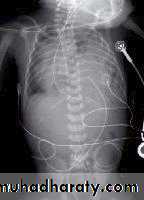

This is a radiograph of a 1-day-old infant with a moderate-sized

congenital diaphragmatic hernia. Note the air- and fluid-filled bowel loopsin the left chest, the moderate shift of the mediastinum into the right chest,